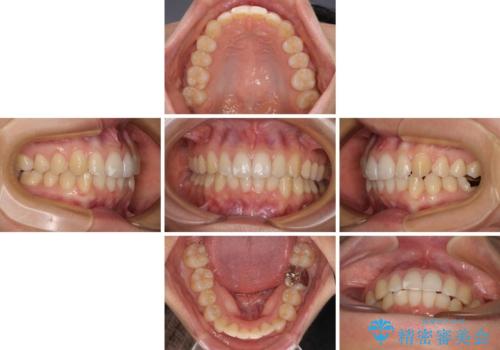

- 上下のクロスバイトと前歯のデコボコを気にして来院された患者様です。

インビザラインを用い、IPR(歯と歯の間を削る)と歯列全体を拡大させることで、歯並びを整えていくこととしました。

下の歯が隠れてしまうほどでしたが、深い咬み合わせも改善され、顎への負担も軽減されました。